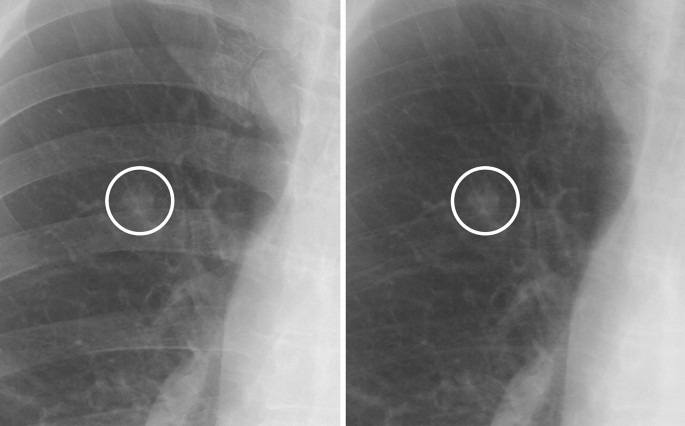

Representative images of nodules that were correctly diagnosed using soft tissue images are shown in Figs. 1, 2, 3 and 4.

A case of a non-calcified nodule overlapping with the bone. (left) On the standard image, the evaluation of the presence or absence of calcification among readers was not consistent (confidence level of each reader: 3, 2, 2, 4 and 2, respectively). (right) In the soft tissue image, the nodule did not disappear. All readers correctly evaluated it as non-calcified (confidence level of each reader, 5, 5, 5, 5 and 4, respectively).